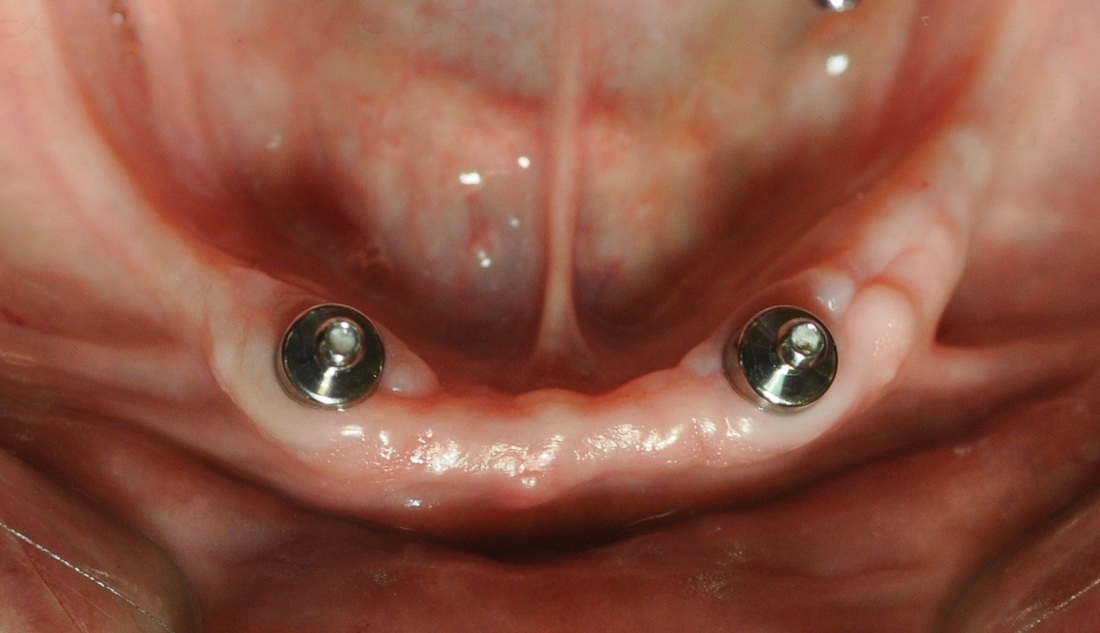

DENTURE STABILIZATION

This patient’s existing old partial denture became loose after one of her teeth had broken. After thorough dental examination Dr. Andrews recommended to extract remaining lower teeth and immediately place two regular size dental implants in order to stabilize a new full lower denture.

During only one surgery three lower teeth were removed, two dental implants were placed. Three months later two snap-on attachments were placed on the integrated implants.

Her speech and chewing ability has instantly significantly improved. The satisfied patient regained quality of life she desired and expressed desire to replace the old upper denture with a new one as well.